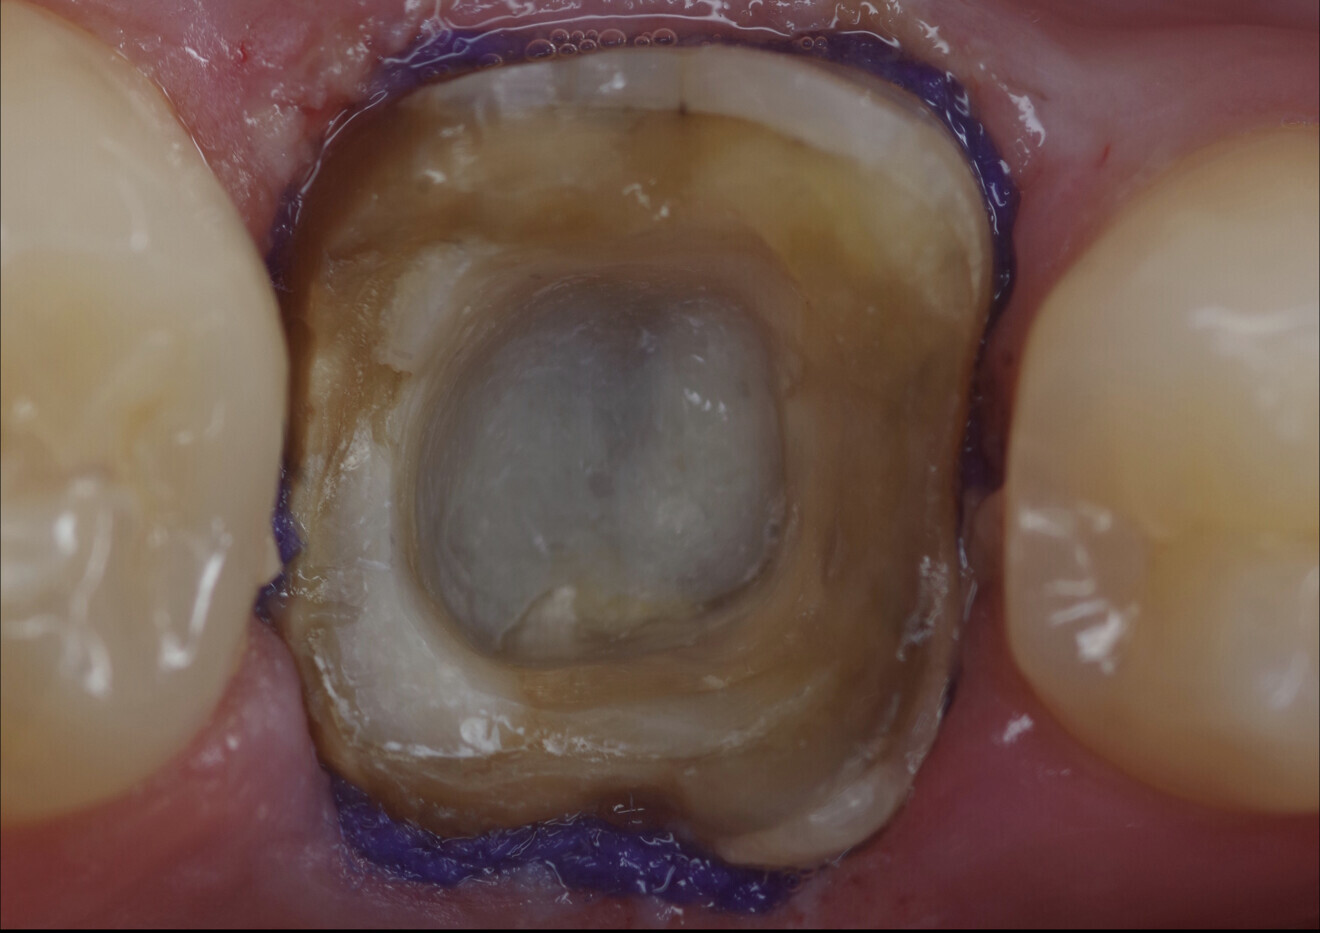

Inner surface of the endocrown. (All image: Drs Alejandro Bertoldi Hepburn & Matías Scazzola)

After the endodontic retreatment, a great loss of tissue was observed in the coronal part of the molar, including the loss of enamel in the distal and lingual sides of the tooth crown, and the residual dentine was thin and strongly discoloured (Fig. 4). Nevertheless, the area that would serve for adhesive bonding to the planned endocrown was large and voluminous. This space, an enlarged pulp chamber, consisted of the original pulp chamber augmented by the access cavity, endodontic instrumentation and iatrogenic tissue removal (Fig. 5).

Fig. 5: Large volume of the enlarged pulp chamber. There were undercuts over the lingual wall. The remaining tissue was thin.

After several try-in tests, the adhesive luting could take place. For this purpose, the inner surface of the endocrown had been previously roughened through sandblasting with 50 µm aluminium oxide particles at 100–200 kPa, cleaned using brushes and distilled water and detergent, rinsed with water and dried with air stream (Fig. 18a). Thereafter, a silane coupling agent (Ceramic Bond, VOCO) was applied and let dry for 60 seconds (Fig. 18b). Once again, retraction cord was placed in the gingival sulcus to displace the free gingivae and prevent fluids from affecting the adhesive process, and Teflon tape was used to protect the neighbouring teeth (Fig. 19).

Figs. 18a & b: Inner surface of the endocrown after sandblasting with aluminium oxide particles, followed by cleaning of the surface with distilled water and detergent (a). Application of Ceramic Bond (b).